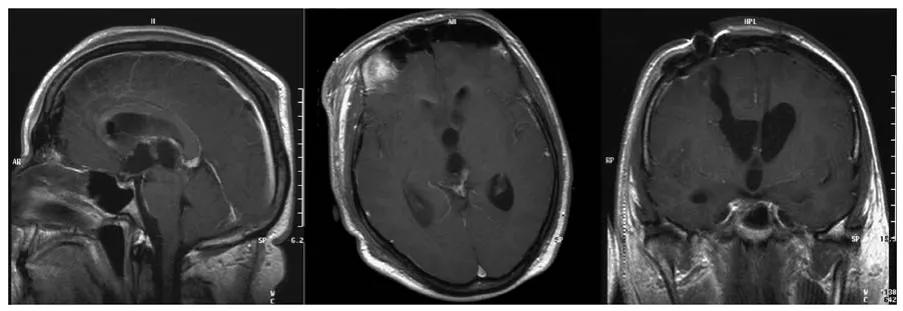

术后磁共振成像显示,第三脑室左侧背侧有少量预期内的肿瘤残留,伴颅内积气,无并发症发生。脑脊液梗阻已解除,4天后拔除了脑室外引流管。术后眼科检查示眼球运动正常,复视消失,左侧视盘仍有水肿,但正在缓慢消退。

图2 术后早期矢状位、轴位及冠状位对比增强磁共振成像扫描